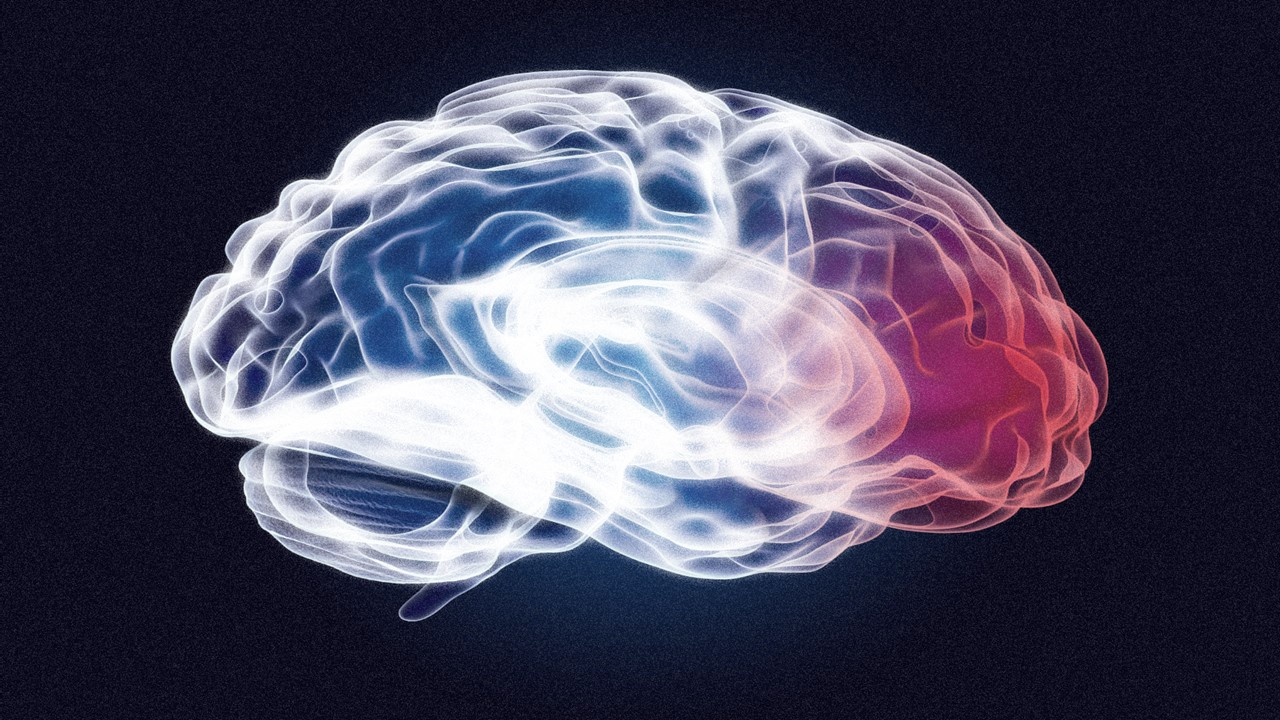

Appreciating the Orphan: Structural Insights Into GPR6 as a Target for Parkinson’s Disease

The discovery of GPR6’s structural and functional properties marks a paradigm shift in Parkinson’s research.

Understanding Lewy Bodies: The Pillars of Parkinson’s Pathology

The recent breakthrough in replicating Lewy body formation in living human neurons marks a pivotal moment in Parkinson’s research.